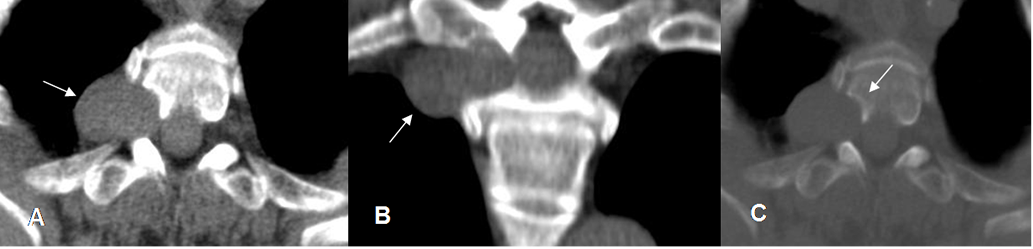

Fig 233. Neurofibroma.

A y C: TAC axial y B: TAC reconstrucción coronal. Lesión sólida y extradural, de bordes bien definidos que ensancha el agujero de conjunción derecho. Hay erosión del cuerpo vertebral, con reborde esclerótico. (Flecha en C).